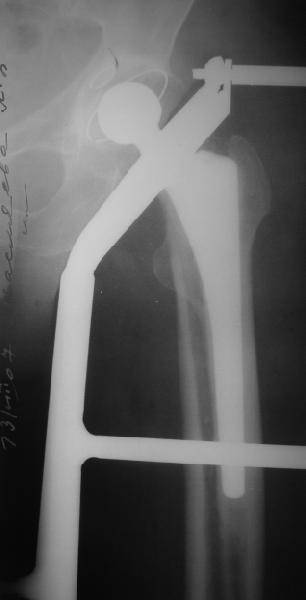

На прошлой неделе пациентке 74 лет, было выполнено цементное эндопротезирование тазобедренного сустава по поводу перелома шейки бедра.Активизирована на следующий день, ходила с костылями, нагрузка полная.Дело близилось к выписке, когда она, подскользнувшись упала в палате и получила то, что  видите на снимках.Что бы Вы стали делать в подобной ситуации? Заранее спасибо.